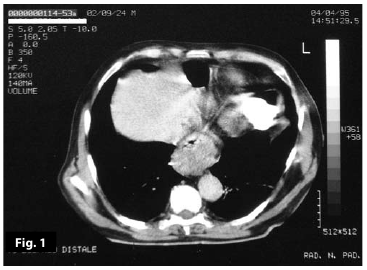

Figure7

Figure7-8

Figure5-6-7-8